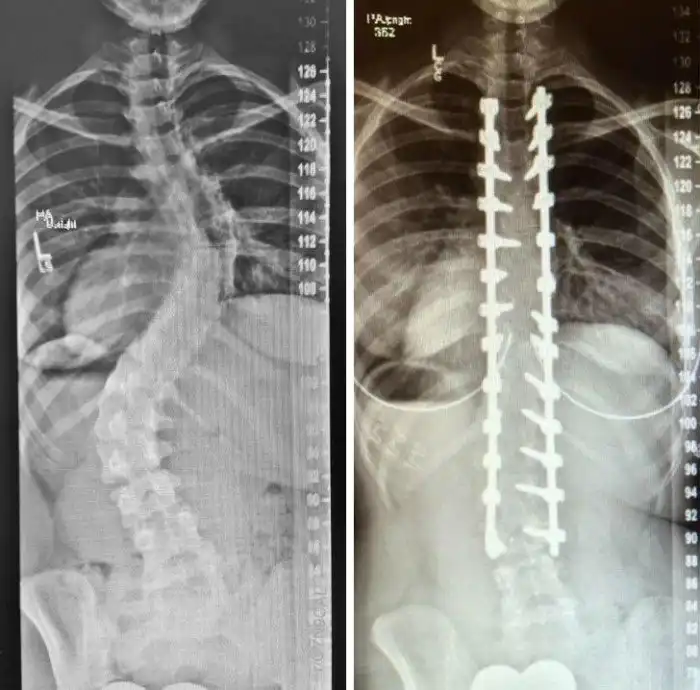

Рентгеновские снимки позвоночника с искривлением: до и после операции